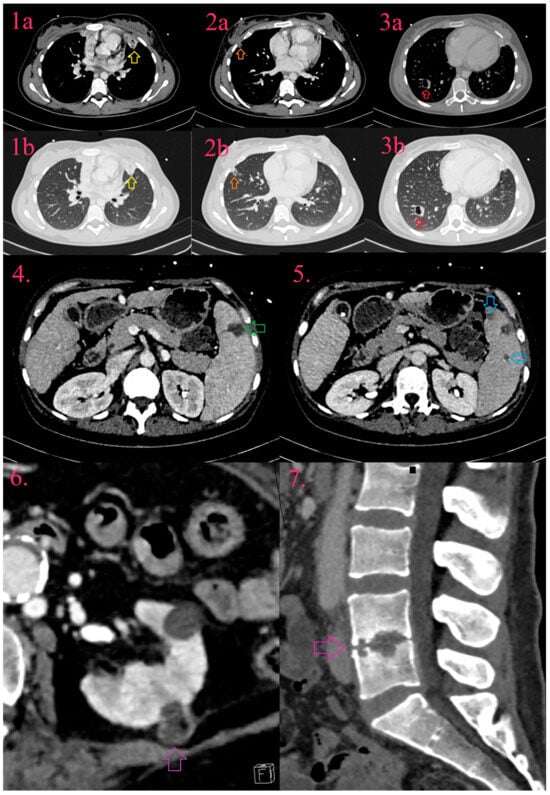

11.2. Thoracic Complications

11.3. Vascular Complications

11.4. Abdominal Complications

11.5. Musculoskeletal Complications